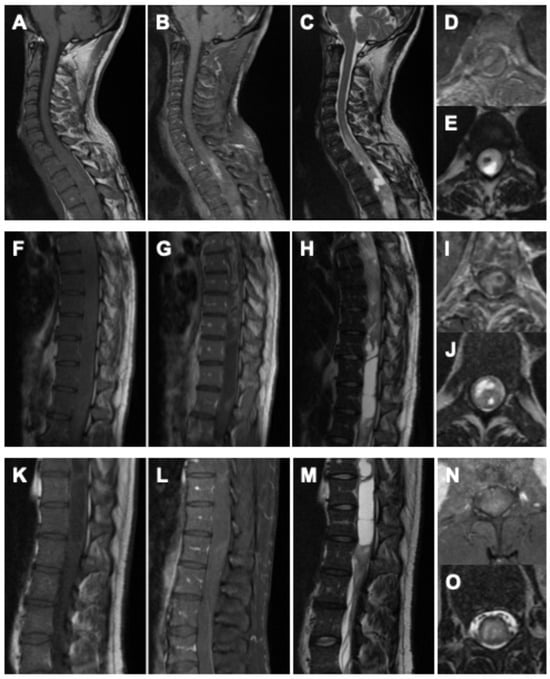

Postoperatively, the patient demonstrated immediate neurological improvement, with motor strength of 3/5 in both lower extremities and recovery of sphincter function. Spasticity and gait disturbance persisted. The postoperative neurological status corresponded to MMS grade IV and KSS 10. MRI following the first surgery revealed diffuse intra-axial contrast enhancement between T3 and T6, residual tumor tissue, and syrinx cavities extending to the conus medullaris (Figure 3A–C).

Figure 3. Postoperative MRI of the spine after the first surgery (AC), showing the thoracic spine in (A) sagittal T2-weighted, (B) sagittal gadolinium-enhanced T1-weighted, and (C) axial T2- and gadolinium-enhanced T1-weighted sequences. Postoperative findings after the second surgery are displayed in (DG): (D) sagittal T2-weighted, (E) sagittal gadolinium-enhanced T1-weighted, (F) axial gadolinium-enhanced T1-weighted MRI of the thoracic spine with indication of the imaging plane, and (G) axial gadolinium-enhanced T1-weighted MRI at the thoracolumbar junction with corresponding imaging plane. Following the second procedure, postoperative MRI confirmed only minimal residual tumor at the levels of T5–T7 and T12/L1, showing marked regression compared with preoperative imaging, accompanied by substantial decompression and regression of the syrinx.

Twelve weeks later, a second procedure was performed, consisting of extended tumor resection from T7 to L1 and complete removal of the remaining shunt catheter (Figure 2). Tumor exposure was achieved via multilevel laminotomies (T6–T12); the laminae were preserved and reinserted at the end of the procedure to maintain the integrity of the posterior spinal elements. The operation proceeded without complications. Neurological examination after the second stage demonstrated substantial functional improvement compared with the preoperative baseline. Muscle strength had increased to 4–4+/5 in both lower extremities, sphincter function was fully restored, and the patient was able to stand with external support. The MMS improved to grade III and the KSS to 16, accompanied by a clear improvement in back and spinal pain control, facilitating mobilization. Postoperative MRI confirmed only minimal residual tumor at the levels of T5–T7 and T12/L1, showing marked regression compared with the preoperative imaging (Figure 3D–G).